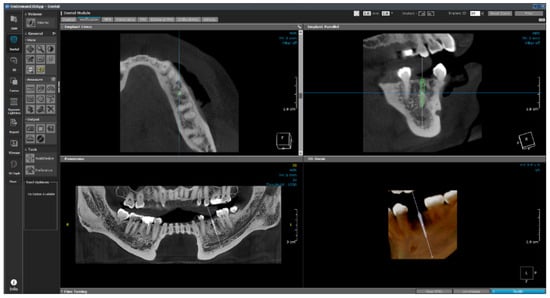

The software consists of modules such as demineralized bone matrix, Dental, 3D, 3D Cephalometric, Fusion, Dynamic LightBox, Report, Xlmage, and In2Guide, and each module functions independently. The dental module applied in this study is the standard for 3D dental reconstruction. This module contains eight different layouts, including dental, verification, multiplanar reformation (MPR), panorama, temporomandibular joint (TMJ), bilateral-TMJ, orthodontic, and airway. As shown in Figure 24, implant surgery can now be fully simulated using the dental module with the help of our real-size library of implant fixtures and abutments as well as the intra-oral/3D model scan data alignment function.

This module plays an auxiliary role for the user by integrating the implant ROM model to provide additional information. All necessary parameters from the implant ROM can be obtained from this module. As shown in Figure 25, the implant to be used is selected from the implant library by selecting the location of the tooth to be installed. Based on the selected location, appropriate bone material property values can be obtained, as shown in Figure 26.

Figure 25. Implant library.